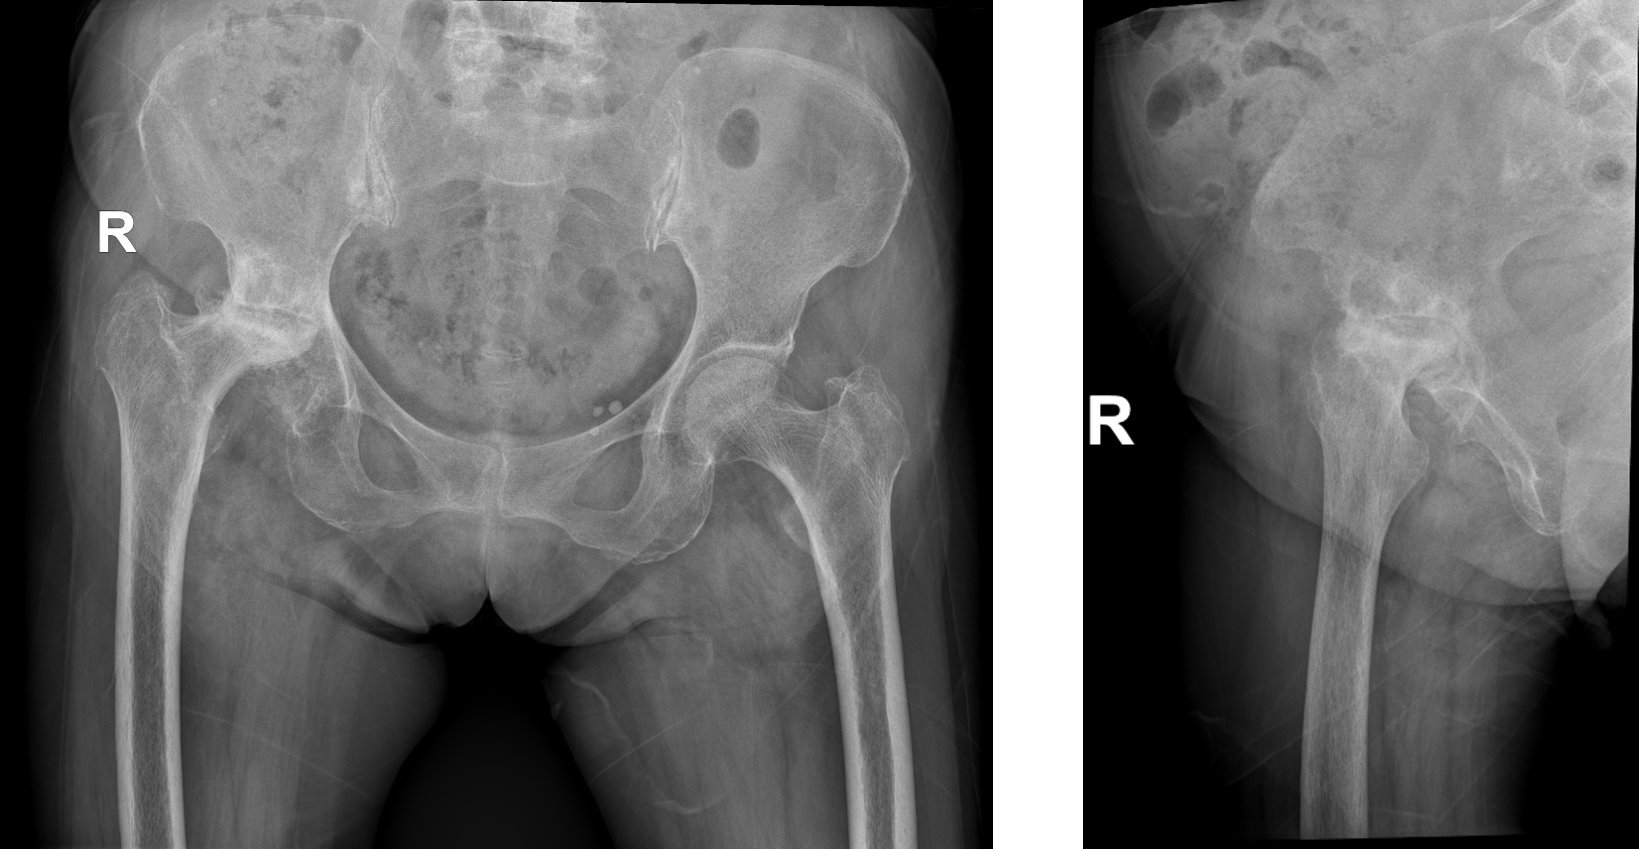

Hip X-ray

- Right hip osteoarthritic changes

- Femoral head osteonecrosis

- Limb length discrepancy

- Interpretation: Advanced hip osteoarthritis